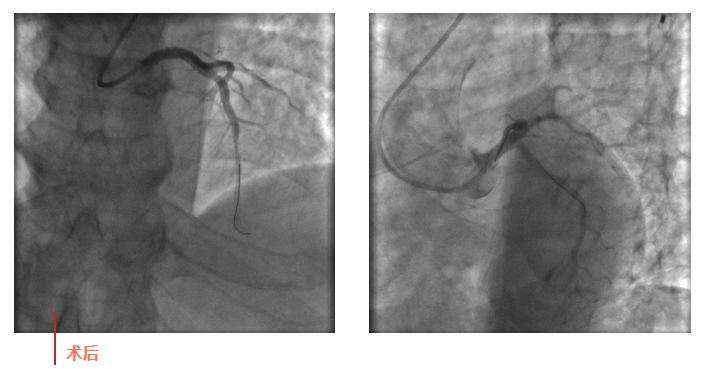

心血管內(nèi)科副主任徐先進在主任助理農(nóng)彥林和主任汪念東的配合下行冠狀動脈造影,結(jié)果如術(shù)前判斷一致,左主干重度狹窄,患者命懸一線。對團隊緊急處置非常信任的李阿姨,毫無疑慮地聽取了術(shù)者的建議,同意在血管內(nèi)超聲(IVUS)的精準(zhǔn)指導(dǎo)下,在患者左主干內(nèi)植入一枚支架,成功拯救了患者的生命。

術(shù)后,患者轉(zhuǎn)入心血管內(nèi)科CCU病房,在IABP泵的支持下渡過了危險期。李阿姨紅著眼眶坐在床邊,仍心有余悸,“還好有你們?。≌媸翘x謝了!”經(jīng)過心血管內(nèi)科團隊的精心治療和護理,患者現(xiàn)已康復(fù)出院。